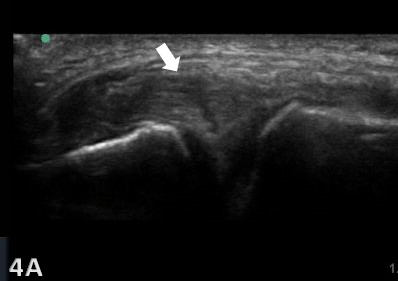

Ultrasound Technique and Diagnostic Criteria for MCL Injuries

MSK-US is highly effective in identifying the presence and severity of MCL injuries. The ligament’s superficial location makes it readily accessible for US examination, which can be enhanced with high-frequency linear transducers to produce detailed soft-tissue images. Dynamic imaging during knee flexion and extension, not possible with MRI, further improves the diagnostic accuracy of US by demonstrating the static functional integrity of the MCL. The examination involves scanning in both longitudinal and transverse orientations, assessing the ligament for echotexture, continuity, and any associated anechoic (fluid) collections indicating acute injury. Diagnostic criteria for MCL injuries are based on ligament thickness, loss of the normal fibrillar pattern, and the presence of preligamentous fluid. One tip when assessing the femoral insertion of the superficial fibers of the MCL is gently tilt the probe along the MCL curved course to avoid the anisotropic effect of a false hypoechogenicity.18